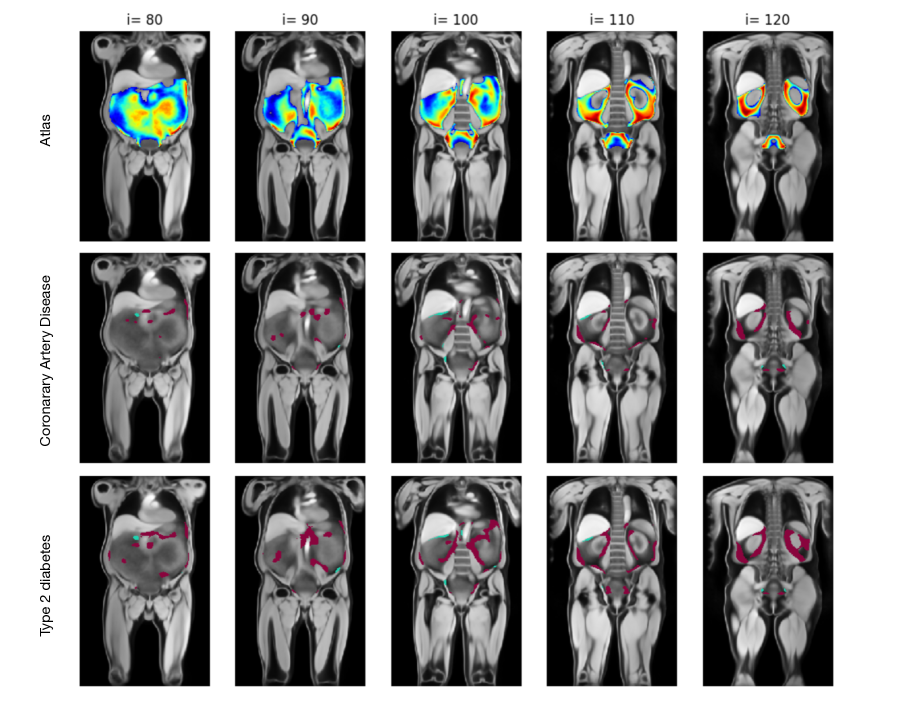

Refer to caption

Figure 6: Significant voxels (p<0.01𝑝0.01p<0.01) in the visceral fatty tissue for patients with coronary artery disease (middle column) and type 2 diabetes (right column) for the male overweight subgroup. The left column shows the atlas, e.g., the average fat distribution, at two slices. The purple pixels in the second and third column represent more fat in the pathological group and cyan less. This shows that there is significantly more visceral fat in the CAD and diabetic group than in the healthy one.

Distributional Changes in Label Atlases

As a second application, we perform a similar analysis with visceral fat distribution. We utilise the abdominal visceral fat maps from healthy subjects previously used to build the atlas of the male overweight group and test them against diseased subjects. The pathological subgroups are selected and registered in the same fashion as previously explained, with the additional criteria that they contain the target disease – in our case, coronary artery disease (CAD) or type 2 diabetes. We select 200200200 subjects with CAD, 200200200 subjects with diabetes and 200200200 subjects from the healthy atlas group. Similarly to before, each fat label map is spatially normalised with a Gaussian kernel, and voxel-wise one-sided t-tests are subsequently performed between the healthy and the pathological group. We perform two types of one-sided t-tests; one assesses a higher mean, which indicates more fat in the pathological group and one the opposite: less fat in the pathological group. The results for both tests are shown in Figure 6, where the significant values for more fat are visualised in purple and those for less fat in cyan. We then perform a FDR correction to the P-map and retain the significant p-values p​v​a​l<0.01π‘π‘£π‘Žπ‘™0.01pval<0.01. Figure 6 shows the significant voxels overlayed on the anatomical atlas for the overweight male subgroup. The first column shows the fat label atlas overlayed on the water-contrast anatomical atlas; the second column shows the significant voxels for more and less fat for CAD; and the last column for type 2 diabetes. Each row is a visualisation of a different coronal slice. A more comprehensive set of slices can be visualised in the supplementary material in Figure 9.

We see a significant increase in organ-associated visceral fat around the kidneys, as well as in mesenteric fat and within the lower pelvis (Figure 9). Areas of lower fat content are found in the marginal area, as well as on the lower liver border. Moreover, comparing both pathological groups, the diabetic group shows a larger increase in mesenteric fat than the CAD group compared to the atlas. This increase in visceral fat for these pathological groups is also observed in other studies[nakamura1994contribution, despres2007cardiovascular], which further confirms the value of these results. We attribute the marginal speckles (e.g., in the shoulders and lungs) to noise arising from either misregistration or remaining false positives from the t-test.